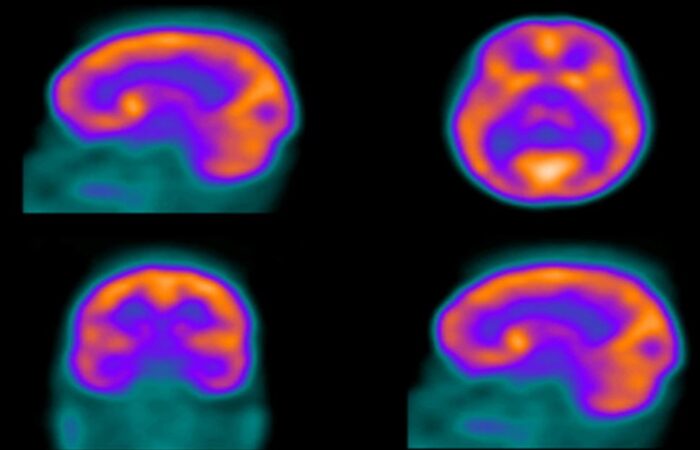

التشخيص النووي بالتصوير الغامي